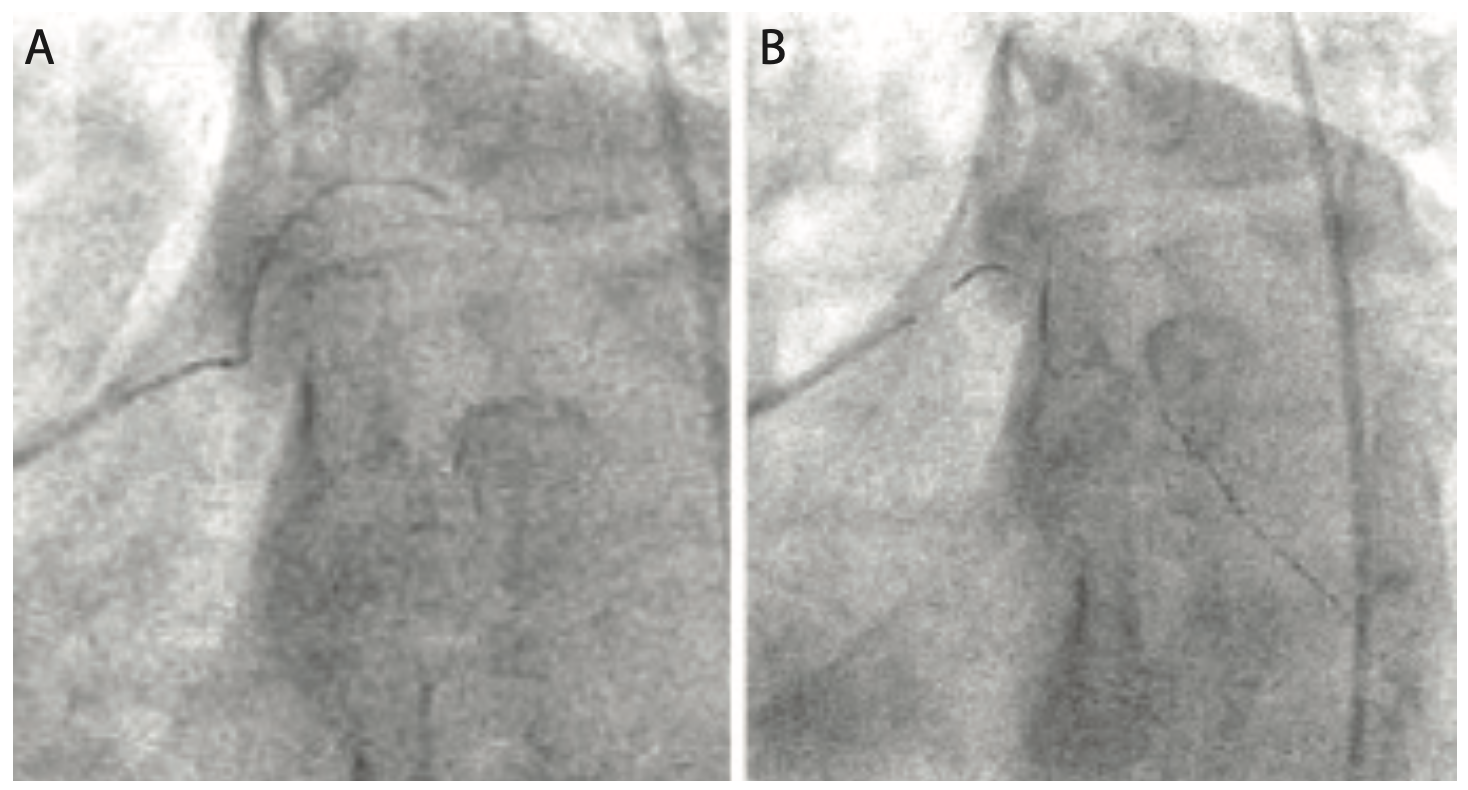

Despite all the efforts to avoid an iatrogenic dissection, the following low injection rate angiography revealed a flow-limiting spiraling dissection extending from the proximal LCx to the OM3 with TIMI-0 flow. The distal LM showed a pseudo-lesion related to wire bias, but there was no dissection proximal to the ostium of the LCx. The stent was deployed using the takeoff of the atrioventricular circumflex branch as a reference, since there was no distal flow to mark adequate distal stent edge positioning (Figure 9 and Video 6). Angiography after distal stent deployment revealed that the stent effectively tacked the distal edge of the spiraling dissection with restoration of TIMI-3 flow (Figure 10 and Video 7).

At this point, the GuideLiner was positioned in the mid LM and a 3.0 mm x 28 mm Xience Alpine drug-eluting stent was meticulously positioned proximally to cover the LCx ostium, which was the proximal site of the dissection, without protruding into the left main and without partially covering the takeoff of the ramus branch (this was possible due to the steep obtuse angle). The proximal stent was overlapping the distal stent by 2 mm (Figure 11 and Video 8). The advancement of the proximal stent was challenging and required a lot of guide catheter support with slow and steady pushing on the stent delivery system.